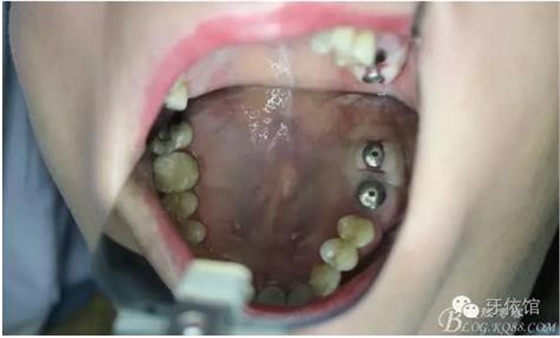

術(shù)后6個月口內(nèi)照

三周后右上6,7